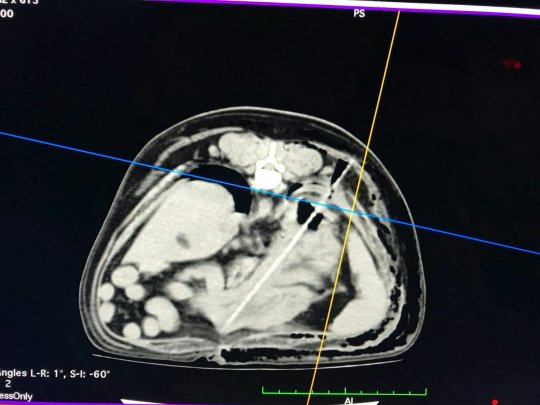

▼獸醫表示從表面看蒙迪沒有任何的異樣,但進行CT掃描時才發現,牠的胸腔裡竟然有一根細長的棍子,這跟棍子已經刺穿了牠的橫膈膜和肺部,需要立即手術,否則將有生命危險。

▼蒙迪在獸醫診所接受了兩個小時的手術,縫了20針,取出異物才知道那根棍子原來是一根烤肉的竹籤。一定是蒙迪在外面偷偷亂吃路邊的烤肉,因為太心急連竹籤也吞了下去,好在手術順利,救了牠一命。